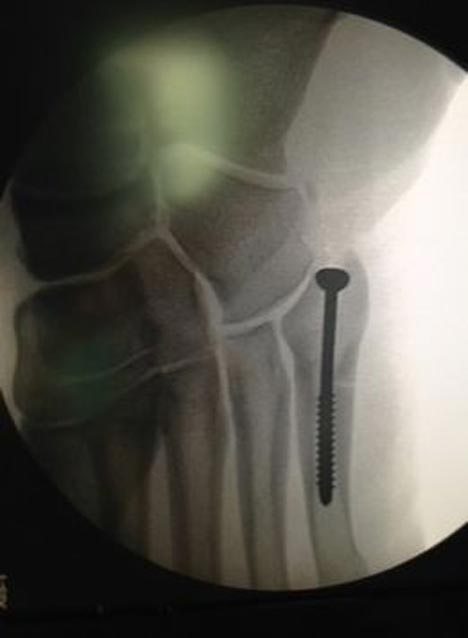

Bola.net - Sebuah skrup titanium dimasukkan dalam kaki kanan Xabi Alonso. Prosedur ini dilakukan untuk menyambung tulang metatarsal kelima Alonso yang retak.

Operasi pemasangan skrup titanium ini hanya memakan waktu 30 menit. Skrup itu dipasang dengan tujuan untuk membuat tulang yang retak stabil dan tidak akan diambil kembali.

Skrup titanium di kaki Alonso. (c) AS